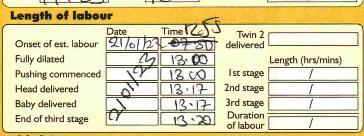

2. CMiS not reflecting the handwritten notes as shown below: -

When the “onset of labour”, “second stage” or ”pushing commenced” fields are not completed in CMiS, the recorded is rejected by MSDS, as you cannot have a vaginal birth without this information. This means I have to access the handwritten notes to establish the timings and add them to CMiS. I may also send you a friendly reminder.

Whenever you enter any data into CMiS, you must ensure it is accurate. I have amended a number of records that have a “delivery decision date” of a whole year before. So if the data was to be believed, this poor person waited a year for their instrumental/operative birth following the decision being made by a doctor!! We all make typos, but it is important to review the data you are adding. Also, if you have students recording information in CMiS, please check the record.